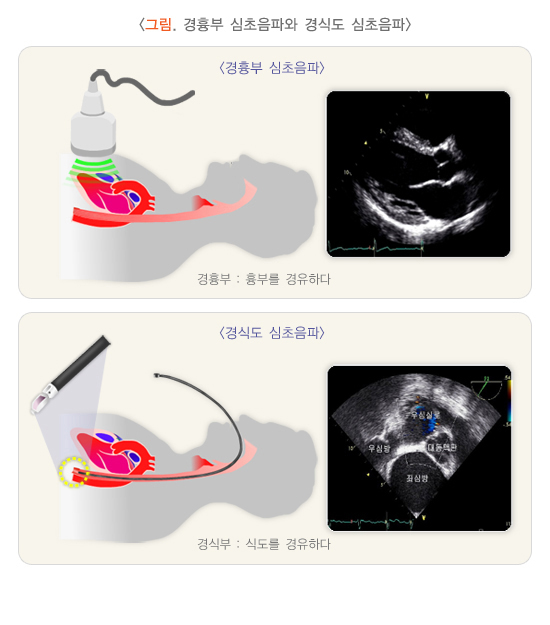

1) 경흉부(transthoracic) 심초음파와 경식도(transesophageal) 심초음파

두 초음파의 원리는 같지만, 경흉부 심초음파(일반적인 심초음파)는 피검사자의 앞가슴에 탐촉자를 위치하여 검사하는 방식이며, 경식도 심초음파는 내시경을 시행하는 방법과 같이 식도 내로 탐촉자를 삽입하여 심장을 검사하는 방식입니다.

일반적으로, 경흉부 심초음파 검사에서 얻은 정보가 불충분하거나, 더 자세한 영상 정보가 필요한 경우에 경식도 심초음파 검사를 시행합니다.